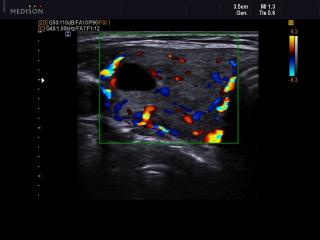

- CD - цветное допплеровское картирование.

- PD - энергетический допплер.

- DPD - направленный энергетический допплер.